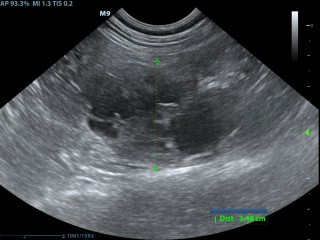

Hieronder zie je een aantal foto's van de buik met achtereenvolgens; blaasontsteking, blaastumor, vroege dracht hond 19 dagen, vergrote eierstok, lever, nier.